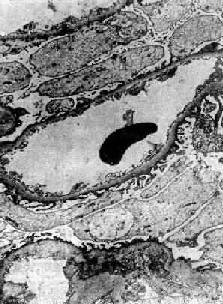

六、轻微病变性肾小球肾炎(脂性肾病)轻微病变性肾小球肾炎(minimal change glomerulonephrits)的病变特点是在光学显微镜下肾小球无明显变化或病变轻微,故名。由于本病肾小管上皮细胞内常有大量脂质沉积,故又称为脂性肾病(lipoid nephrosis)。临床上常表现为肾病综合征。脂性肾病多见于小儿,成人患者较少,是引起小儿肾病综合征最常见的原因。在小儿肾病综合征中约65%~85%由脂性肾病引起。成人肾病综合征由脂性肾病引起者约占10%~30%。脂性肾病病变可完全恢复,对皮质激素治疗效果很好。 轻微病变性肾炎与其他类型肾炎不同,电镜观察未找到沉积物,免疫荧光检查也未发现肾小球内有免疫球蛋白或补体。其病因和发病机制尚不清楚。有些现象如有些病人在呼吸道感染后发病,或同时伴有其他过敏性疾病,如过敏性鼻炎和湿疹等,提示可能与免疫机制有关。Hodgkin病患者轻微病变性肾炎发病率较高,而已知Hodgkin病患者常有T细胞功能缺陷,故有人认为这种肾炎的发病可能与T细胞功能异常有关。近来有学者提出,肾小球多聚阴离子减少可能是造成本病肾小球毛细血管上皮细胞变化和大量蛋白尿的原因。 【病理变化】 光学显微镜下,肾小球无明显变化或仅有轻度节段性系膜增生。电镜下见弥漫性肾小球脏层上皮细胞足突消失(图12-20),细胞内高尔基器和内质网增多,并可见脂滴。细胞表面常有多数微绒毛形成。足突消失不仅见于脂性肾病,也常见于其他原因引起的大量蛋白尿和肾病综合征。经过治疗或蛋白尿等症状缓解后,脏层上皮细胞的变化可恢复正常。

图12-20 轻微病变性肾小球肾炎 电镜下见肾小球毛细血管上皮细胞部分足突消失 肾小管上皮细胞内有多数玻璃样小滴和脂类沉积,是由于肾小球毛细血管通透性增加,大量脂蛋白通过肾小球滤出,而在肾小管被重吸收所致。肾小管腔内可有透明管型。这些变化常与蛋白尿的程度平行。 肉眼观,肾肿胀,体积较大,色苍白。由于大量脂类沉着,切面可见黄色条纹。 【临床病理联系】 脂性肾病病人临床上大多表现为肾病综合征,有大量蛋白尿和严重水肿,与膜性肾小球肾炎不同的是,蛋白尿为高度选择性,主要含小分子蛋白,如白蛋白。肾小球的病变轻微,故一般无血尿和高血压,肾功能也不受影响。 【结局】 大多数病人对皮质激素治疗效果很好,90%以上儿童可以完全恢复,病变在数周内消失。成人预后也很好。少数病人可有反复,一般不发展成慢性。